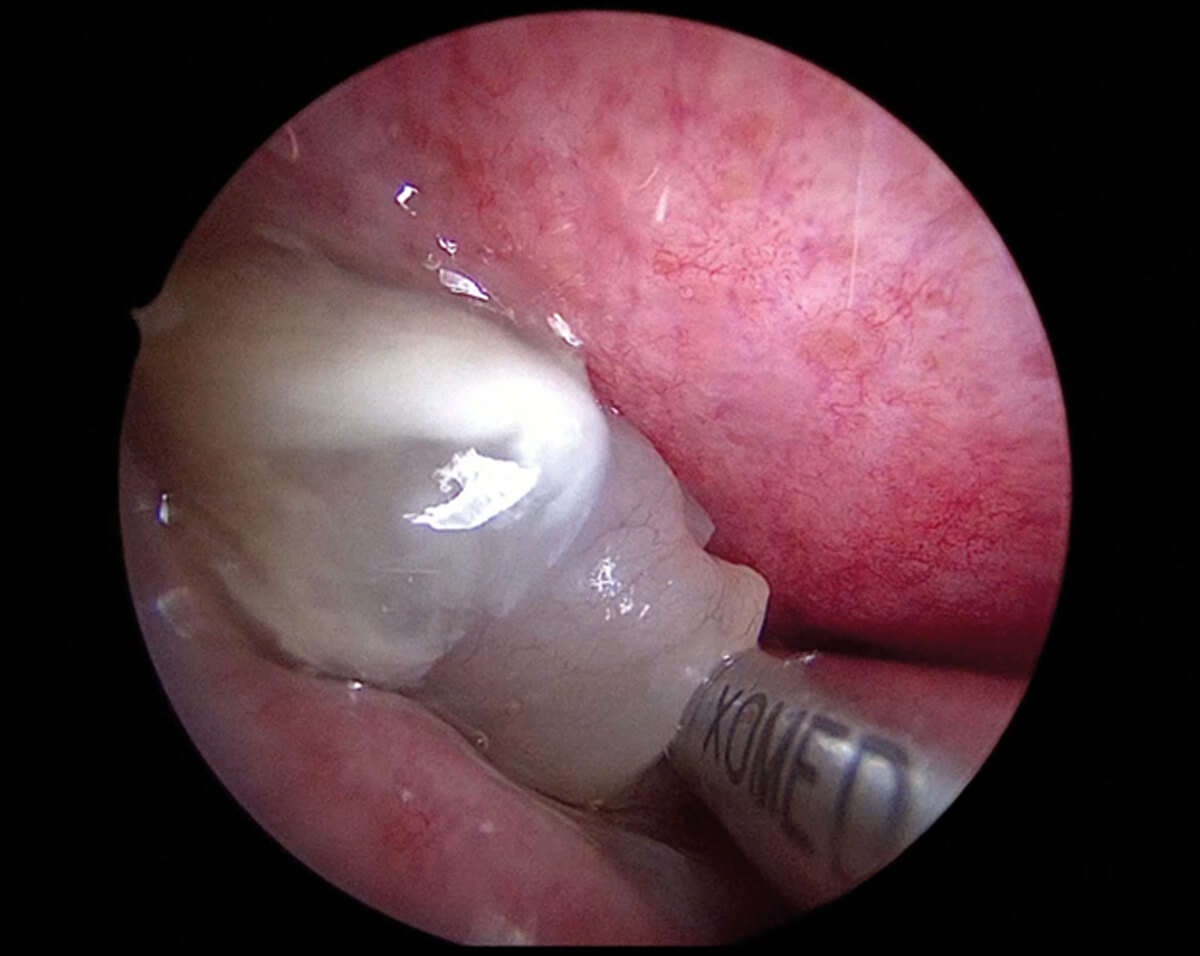

Polypectomy under local anaesthesia using a 2.9mm thin blade microdebrider.

To date, nasal polypectomy is the most valuable procedure in awake rhinology. This well-tolerated procedure provides rapid relief to patients with chronic rhinosinusitis with nasal polyps. Polypectomy under local anaesthesia is a solid alternative to repeated ethmoidectomies that were sometimes done before. It’s also a good first choice for patients who can’t have general anaesthesia or who mainly complain about nasal blockage from polyps. Utilising a microdebrider with a thin blade (Medtronic® 2.9 mm blade, Dublin, Ireland), the polyps can be safely removed. Since polyps lack nerve fibres, this procedure is generally well tolerated. Bleeding control is a key aspect of this procedure, especially under local anaesthesia. We perform nasal packing with a vasoconstrictor (naphazoline) combined with 5% xylocaine for 20 minutes prior to the surgery to limit bleeding.

In most cases, small amounts of bleeding can easily be suctioned by the microdebrider. In addition, posterior nasal packing can be used to prevent inhalation in the event of significant intraoperative bleeding. This minimally invasive approach allows for real-time assessment and promotes rapid recovery. Studies have demonstrated that such procedures are safe and effective, with significant improvements in nasal obstruction observed postoperatively. Additionally, patient-reported experience measures indicate high satisfaction rates, with many patients preferring local anaesthesia over general anaesthesia for polypectomy. The average duration of symptom relief post-procedure extends beyond two years, underscoring the long-term efficacy of this approach [2].